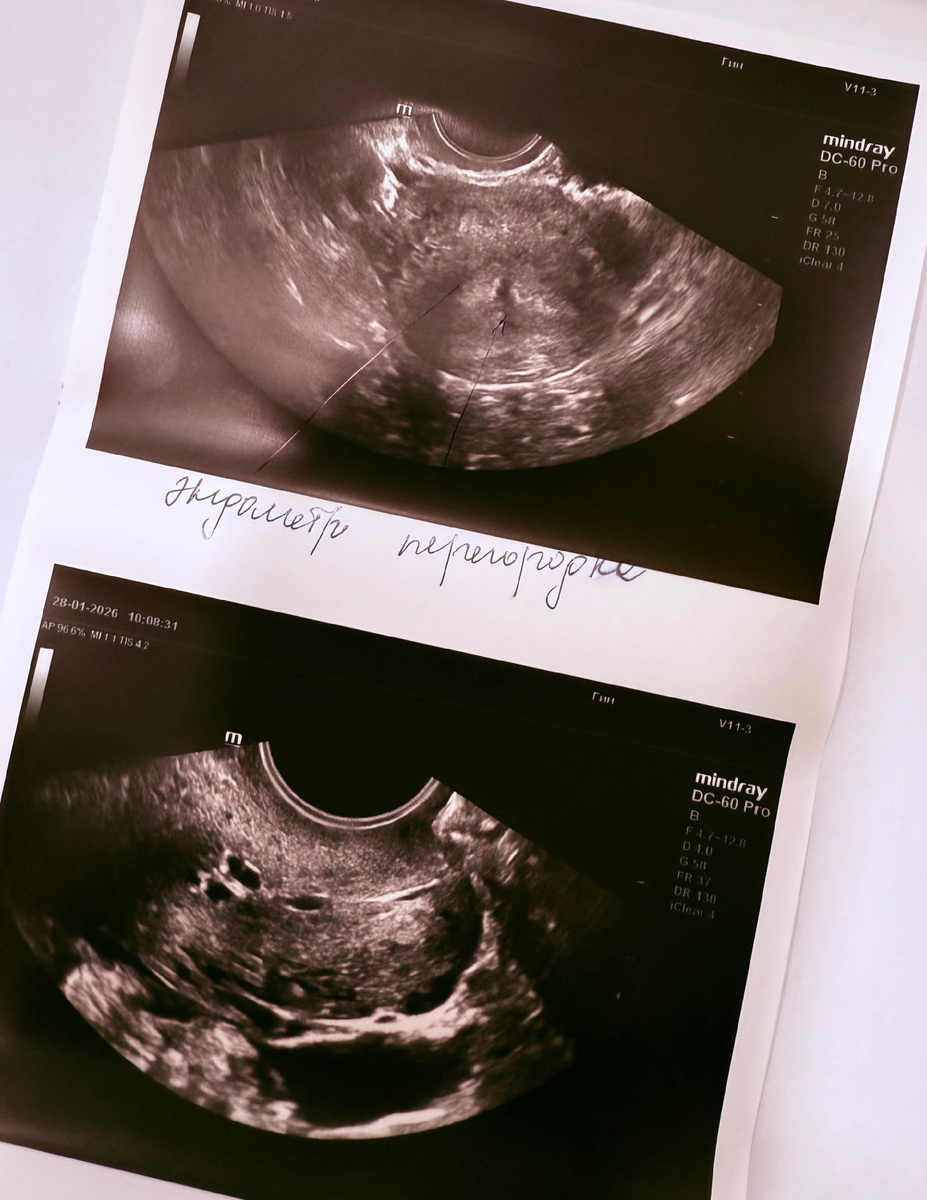

По УЗИ поликистоз яичников сохранялся, рубец на матке, вполне себе полноценный; и, вроде как, выявилась неполная перегородка в матке. Возможно, это тоже было одной из причин бесплодия.